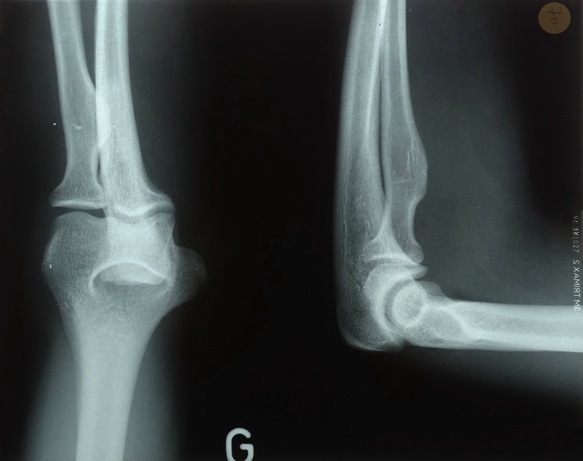

Analyse de radiographies

Analyse différentes radiographies. Essaye de reconnaître:

les différentes parties représentées: os, articulations,...

les malformations, les déplacements, les fractures.

l’âge des sujets: zones de croissances.